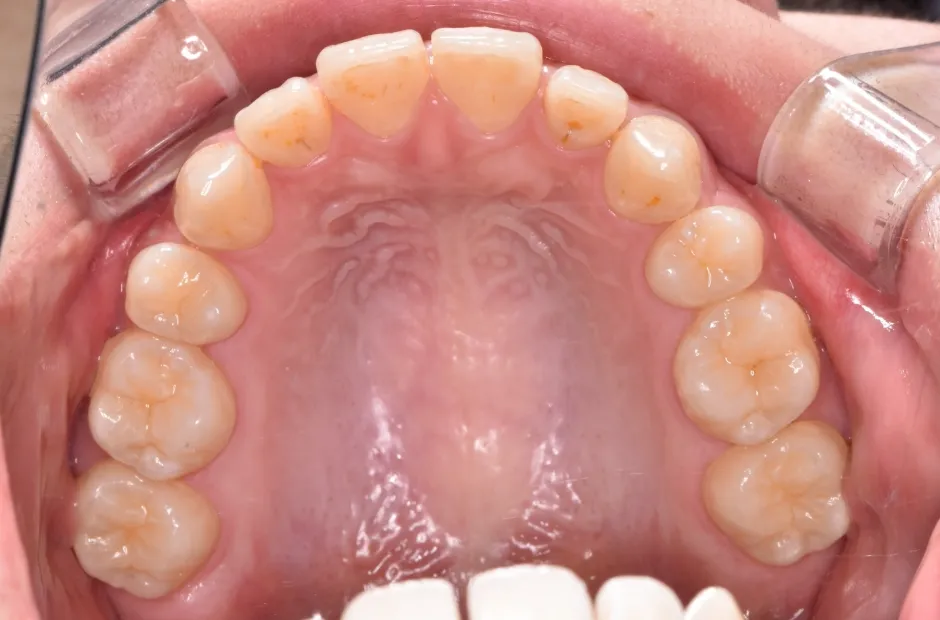

叢生

| 診断名・主訴 | 叢生 |

|---|---|

| 年齢・性別 | 43歳・女性 |

| 治療期間・回数 | 2年7か月 27回 |

| 治療に用いた主な装置 | 舌側矯正 |

| 抜歯部位 | 両顎4,4 |

| 治療費 | 100万円(税抜) |

| リスク・副作用 | 装置による違和感・疼痛・歯肉退縮・歯根吸収・虫歯のリスクなど |

治療前